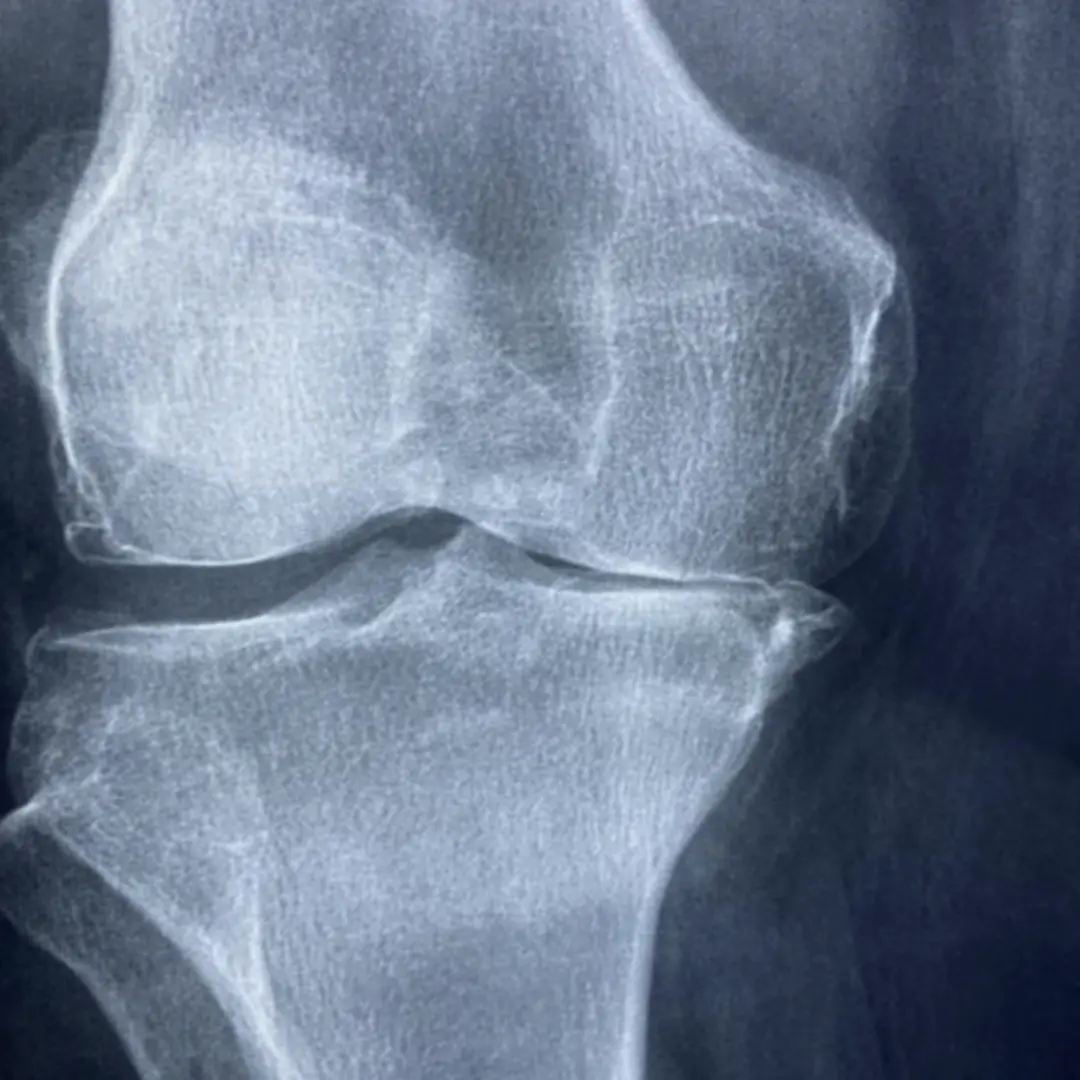

- 관절 연골 보호:

- 연골의 수분 보유 능력을 높여 연골이 마모되는 것을 막아줘요.

- 연골 세포의 생성과 유지를 도와 관절 기능 개선에 효과적입니다.

- 관절 통증 완화:

- 관절 염증을 줄여 통증 완화에 도움을 줘요.

- 관절의 움직임을 부드럽게 하여 활동성을 높여줍니다.

- 골관절염 개선:

- 골관절염 진행 속도를 늦추고 증상 완화에 효과적인 도움을 줄 수 있어요.

- 관절의 기능을 개선하여 일상생활의 불편함을 줄여줍니다.